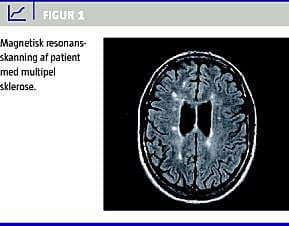

Ætiologien til depression hos MS-patienter kan for ca. 40% forklares af organiske skader, der er påvist ved magnetisk resonans (MR)-skanning (Figur 1 ). Andre forklarende forhold kan være de psykosociale forhold, herunder usikkerhed og bekymring i forhold til fremtiden, handikappets omfang, sociale konsekvenser og evnen til følelsesmæssigt at klare en kronisk sygdom [8, 9]. Herudover har man fundet sammenhæng mellem depression og endokrin dysfunktion, autoimmune dysregulationer, kognitiv dysfunktion og træthed [10].